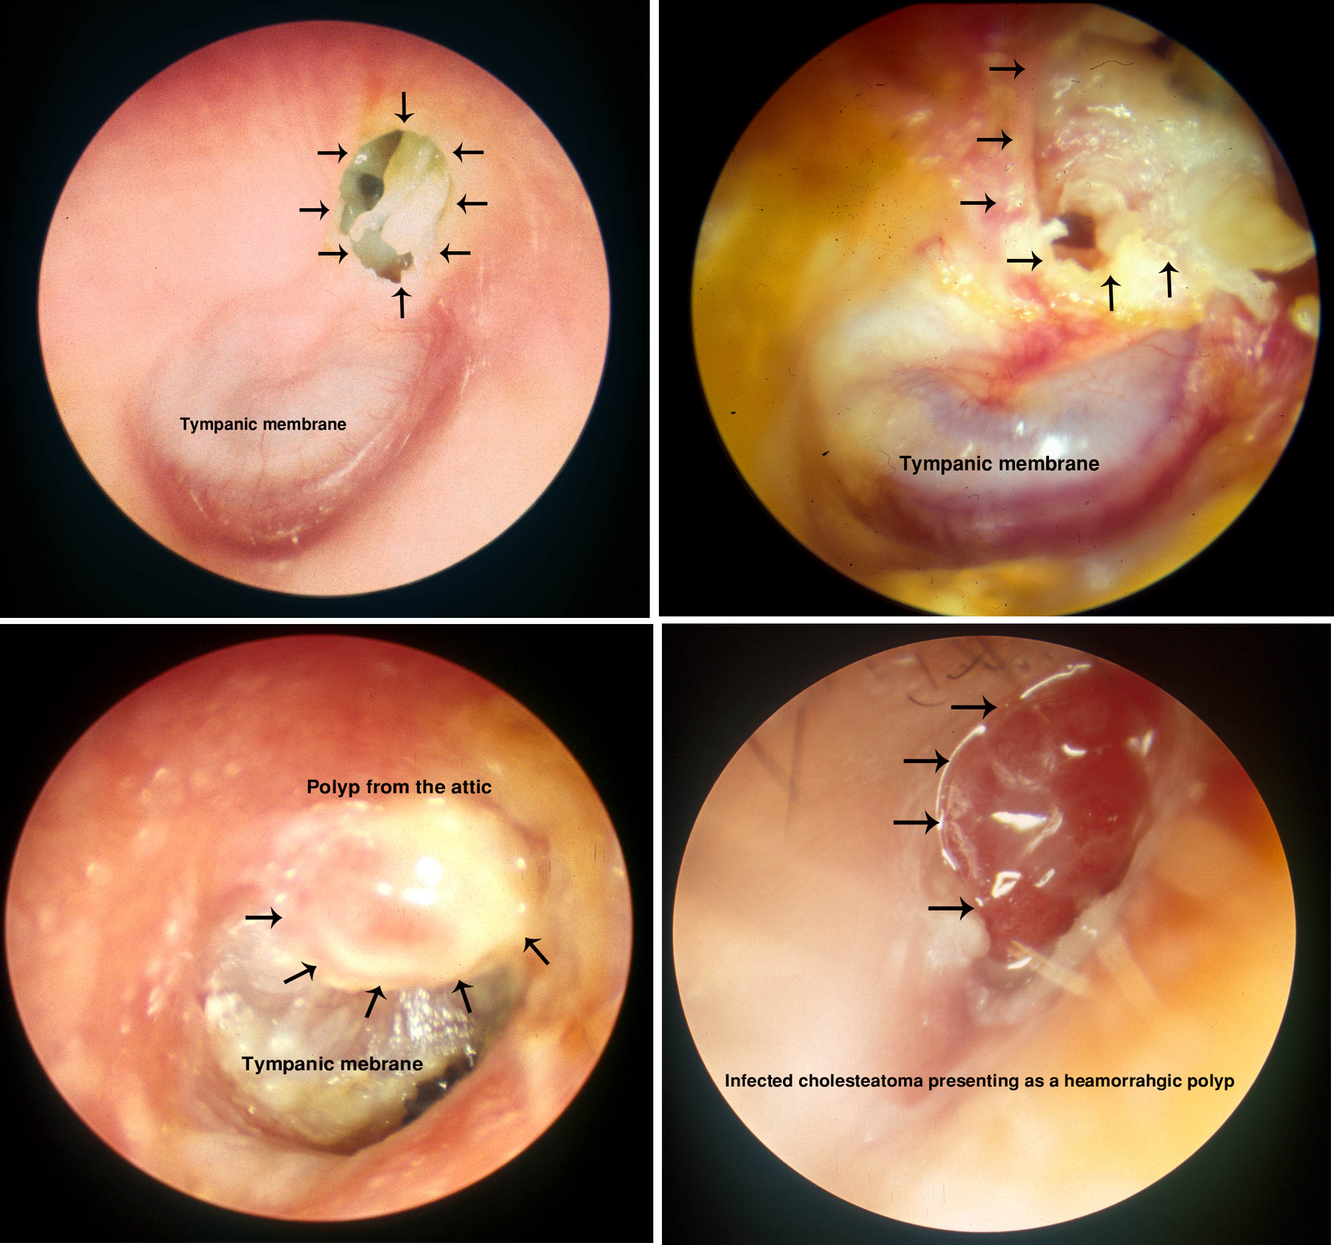

Cholesteatoma